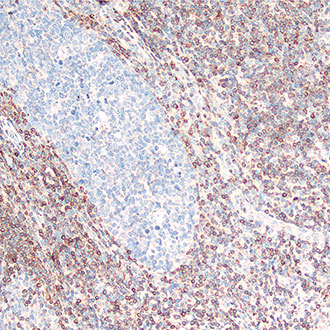

CD45

CD45 -